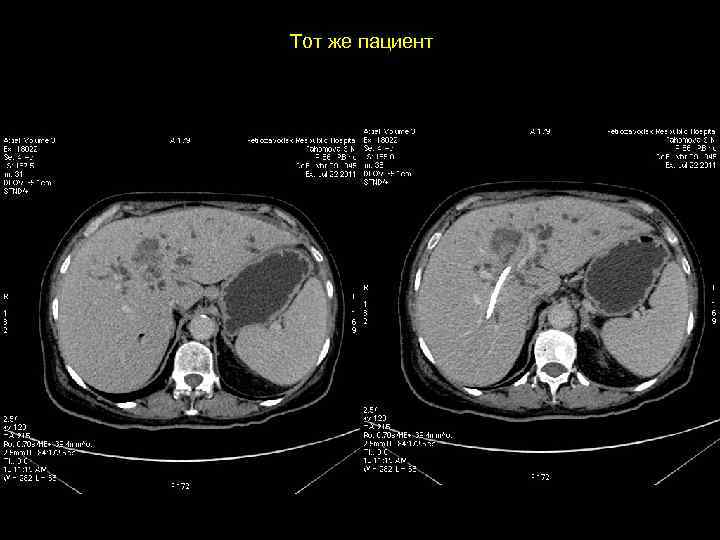

Тот же пациент